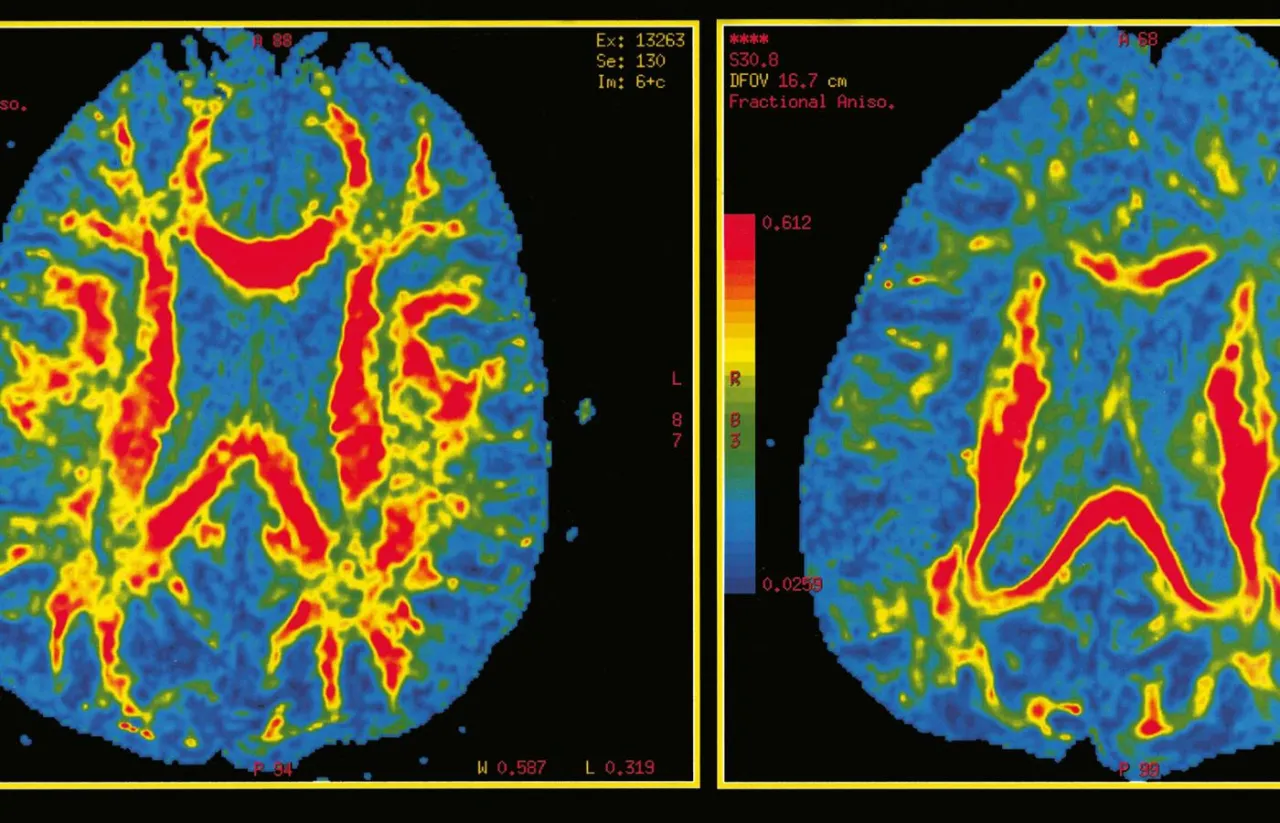

Podstawą diagnostyki jest szczegółowy wywiad lekarski, podczas którego lekarz zbiera informacje o objawach, historii choroby i stylu życia pacjenta. Następnie przeprowadzana jest ocena neuropsychologiczna, która bada funkcje poznawcze, takie jak pamięć, uwaga, mowa czy zdolności przestrzenne. Kluczowe są również badania obrazowe mózgu, takie jak rezonans magnetyczny (MRI) lub pozytonowa tomografia emisyjna (PET), które pozwalają na wizualizację zmian w strukturze i funkcjonowaniu mózgu. Czasami wykonuje się także analizę płynu mózgowo-rdzeniowego (likworu), aby wykryć specyficzne markery choroby.